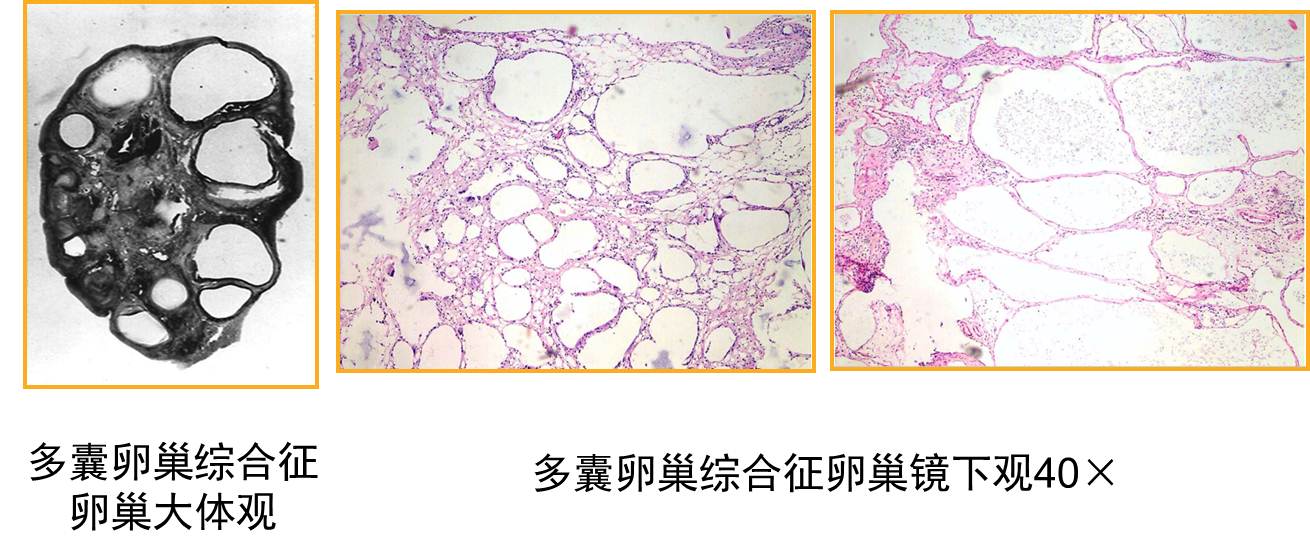

【病理】

1.卵巢变化 大体检查:双侧卵巢均匀性增大,为正常妇女的2~5倍,呈灰白色,包膜增厚、坚韧。切面见卵巢白膜均匀性增厚,较正常厚2~4倍,白膜下可见大小不等、≥12个囊性卵泡,直径在2~9mm。镜下见白膜增厚、硬化,皮质表层纤维化,细胞少,血管显著存在。白膜下见多个不成熟阶段呈囊性扩张的卵泡及闭锁卵泡,无成熟卵泡生成及排卵迹象。